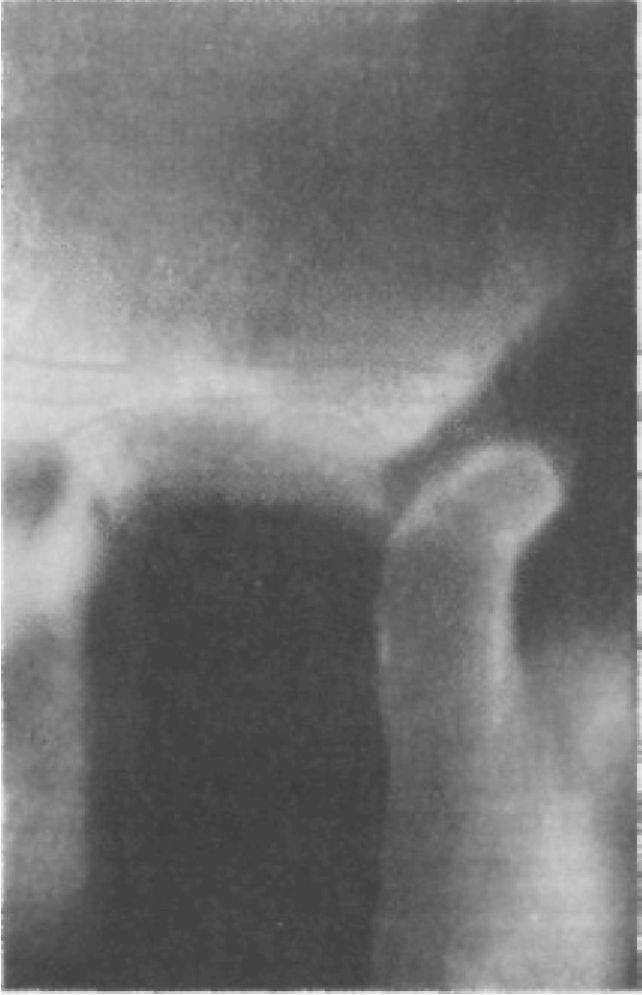

Рис. 183. Положение вывихнутой головки нижней челюсти. Боковая томограмма.

Причины и условия возникновения вывиха нижней челюсти разнообразны: травмы, последствия воспалительных, дистрофических процес-.

сов в суставе, нервно-мышечные нарушения челюстно-лицевой области, врожденные аномалии развития ВНЧС. При травмах возникают острые вывихи нижней челюсти, а под влиянием других перечисленных факторов развиваются хронические вывихи, которые получили название привычных вывихов. Основными патогенетическими звеньями привычных вывихов являются чрезмерное растяжение мышечно-связочного аппарата и капсулы сустава, изменение формы, размеров и структуры внутрисуставного диска, деформация костных элементов сустава. В результате этих изменений наиболее часто происходят передние вывихи. Они возникают при зевоте, крике, откусывании пищевого комка; при стоматологических или иных лечебных вмешательствах, связанных с широким открыванием рта: удаление зубов, снятие оттисков, интубация трахеи и т. п.